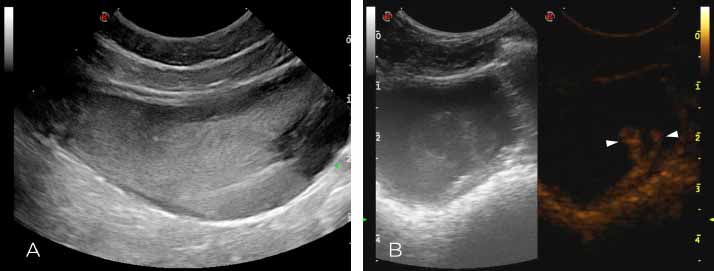

Fig. 1. Long-axis view of the urinary bladder on B-mode (A) and side-by-side B-mode (left) and contrast-mode (right) after administration of contrast agent at the level of the right UVJ (B) A—Notice the large amount of suspended echogenic material occupying most of the lumen of the urinary bladder. B—Notice the large amount of echogenic ill-defined material projecting into the urinary bladder lumen from the right UVJ in fundamental mode (left). This material is markedly contrast-enhancing and more conspicuous with harmonic mode (right; white arrowheads).

An 8-year-old female neutered Whippet was presented to the Royal (Dick) School of Veterinary Studies (University of Edinburgh) for investigation of a 4-week history of chronic intermittent macroscopic hematuria. The dog had no other lower urinary tract signs and the urine appeared discolored during all the micturition with occasional visible blood clots. The dog received regular flea treatment; vaccination and deworming were up to date. There was no previous history of a bleeding predisposition or trauma. No history of traveling overseas nor history of tick exposure was reported. The dog had been treated by the referring veterinarian surgeon (RVS) with a short course of non-steroidal anti-inflammatories and potentiated amoxycillin with no improvement of the clinical signs. Extensive investigations prior to referral were performed by the RVS and included the following: urinalysis revealed urine specific gravity (USG) of 1.055, pH 6, blood 3+, and protein 3+; urine sediment revealed a large amount of red blood cells. The bacteriologic culture of the urine resulted negative. Hematology and serum biochemistry revealed a mild increase in urea (8.2 mmol/l, reference 1.7–7.40 mmol/l), mildly increased hemoglobin at 19.7 g/dl (12.00–18.00 g/dl), and hematocrit at 58.0% (37%–55%) suspected to be breed-related. Platelet count was normal. Plain abdominal radiographs of the abdomen, pneumocystogram, and double-contrast cystography had revealed no abnormalities other than an intrapelvic location of the urinary bladder silhouette of equivocal clinical significance. On presentation to our referral center, physical examination was unremarkable, but signs of discomfort were elicited upon palpation of the dorsocaudal abdomen. Differential diagnoses considered for hematuria included a clotting disorder, urinary tract infection or pyelonephritis, neoplasia, trauma, urolithiasis, or IRH. Repeat complete blood count and serum biochemistry were within normal limits. Prothrombin time, activated partial thromboplastin time, D-dimers, and fibrinogen were within the reference intervals. Buccal mucosal bleeding time was less than 4 minutes. Systolic blood pressure was mildly increased (165 mmHg) but not considered high enough to be the cause of bleeding. Repeated urinalysis from both a free catch and a cystocentesis urine sample showed similar findings: macroscopic hematuria, USG of 1.040, pH 7, protein 3+, and blood 3+. Sediment showed large amounts of erythrocytes with no signs of crystals, casts, or inflammatory cells. Hemoglobinuria or myoglobinuria was excluded by centrifugation. Repeat urinary culture resulted in no bacterial growth. Thoracic radiographs, performed to rule out neoplastic/metastatic changes, were unremarkable. B-mode full abdominal ultrasound and CEUS study of the urinary system were performed using a multifrequency microconvex transducer (CA 123 Esaote, Genova, Italy). On CEUS, the mechanical index was set at minimum (0.08) and only a single focal zone was positioned, directly below each kidney and urinary bladder. A second-generation contrast agent (SonoVue© Bracco, Milano, Italy) was injected as a bolus into the cephalic vein through an angiocatheter, to evaluate the entire urinary tract. Two different boluses of 0.06 ml/kg were administered at 10 minutes intervals, followed by injection of a bolus of 3 ml of 0.9% sodium chloride flush. Images were stored digitally and subsequently analyzed. Moderate amount of suspended echogenic material was visible in the urinary bladder lumen in B-mode (Fig. 1A). During pre-contrast B-mode imaging, the jets from the UVJs were not clearly seen. On CEUS, an intermittent jet of echogenic material from the right-UVJ was noted in the fundamental mode. This finding was more conspicuous with harmonic imaging where intermittent excretion of markedly enhancing mobile material was visible from the right-UVJ (Fig. 1B). No evidence of hyperechoic fountain-like material emerging from the left ureteric orifice was detected. Normal enhancement of the urinary bladder wall was detected with hyperenhancing submucosal layer, serosal layers, and hypoenhancing muscular layer. On B-mode and CEUS ureters, urethra and urinary bladder wall were unremarkable. Kidneys showed a normal architecture, size, and echogenicity, apart for a single left renal cortical cyst (2 mm) that was considered an incidental finding. Contrast study of both kidneys was also unremarkable with a progressive cortical, corticomedullary, and washout phase. The ultrasonographic findings were indicative of urinary bladder sedimentation most likely consistent with hematuria, likely secondary to active upper urinary tract bleeding from the right nephro-ureteral tract. The most likely differential diagnosis considered was idiopathic renal/ureteral hematuria. Infectious diseases affecting the urogenital tract were excluded due to the negative microbiology exam of the urine. The presence of a neoplastic disease or occult urolithiasis was considered unlikely due to the absence of crystalluria, normal abdominal radiography and normal B-mode, and CEUS studies of the urinary system.